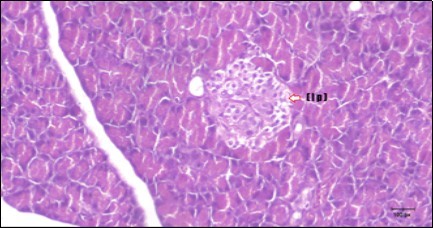

Pancreas Histopathological Observations

Histological examination of pancreas of the control rats showed normal sized islets of pancreas (Ip) compared to the diabetic rats which showed markedly atrophic islets of pancreas (I.p.) (Figure 8 and Figure 9). Pancreas of in groups (3) and (4) rats showed mild atrophic islets of pancreas (I.p.) with inflammatory cellular infiltrate (Figure 10 and Figure 11). The pancreas of rats in group (5) showed nearly normal islets of pancreas (I.p.) with few inflammatory cellular infiltrate (I.c.) (Figure 12).

Figure 12.Photomicrogragh of pancreas section of treated rat with both Fenugreek and Glimepiride showing nearly normal islets of Langerhans with spindle (arrow) & polygonal cells (dashed- arrow). (H&E) (40x).

Histopathological observation in diabetic control showed degenerative changes in both endocrine and exocrine pancreases. A probable explanation may be related to oxidative stress resulting from hyperglycemia which decreases the antioxidants levels and increases ROS 33 and the activities of antioxidant enzyme were altered in diabetic rats. These effects further exacerbate the development and progression of diabetes complications and these may represent the causes of degeneration revealed in histological sections. Fenugreek improved blood glucose levels and insulin, lowered pancreatic islet and β-cells damage which may be attributed to its immune modulatory activity and insulin stimulation action along with its antioxidant potential 32. Glimepiride caused restoration of morphology of beta cell of diabetic and it increased percentage of beta cells 34. This protective effect could be attributed to the antioxidant properties of Glimepiride. Combination therapy improves the protective effect of both therapies alone.